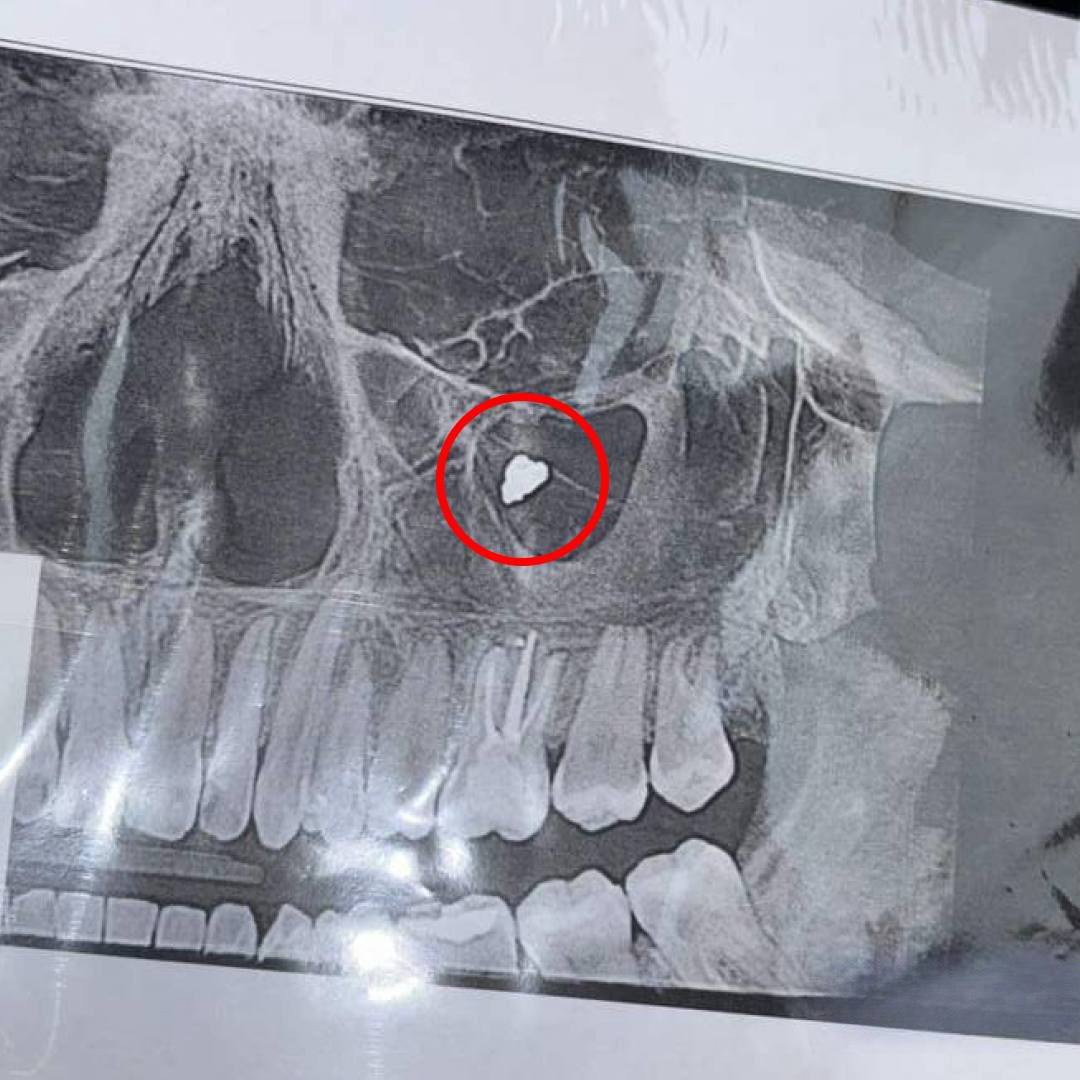

Снимок и обнаружил проблему, которая, как оказалась возникла еще несколько лет назад после сложного лечения зуба, когда врач перепломбировал каналы. Инородный материал застрял пазухе. Пациентке потребовалась операция.